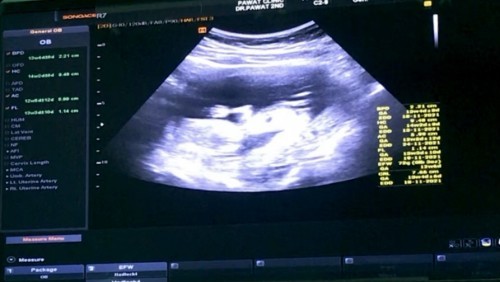

อายุครรภ์13+4 น้ำหนักขึ้นมาเกือบ6โลเลย แม่ชอบกินมากกกกตรวจฉี่น้ำตาลขึ้นมา3+เลย โดนงดเรียบร้อยค้า😅 ✌🏻#ตัวเล็กโบกมือให้ด้วย👶🏻